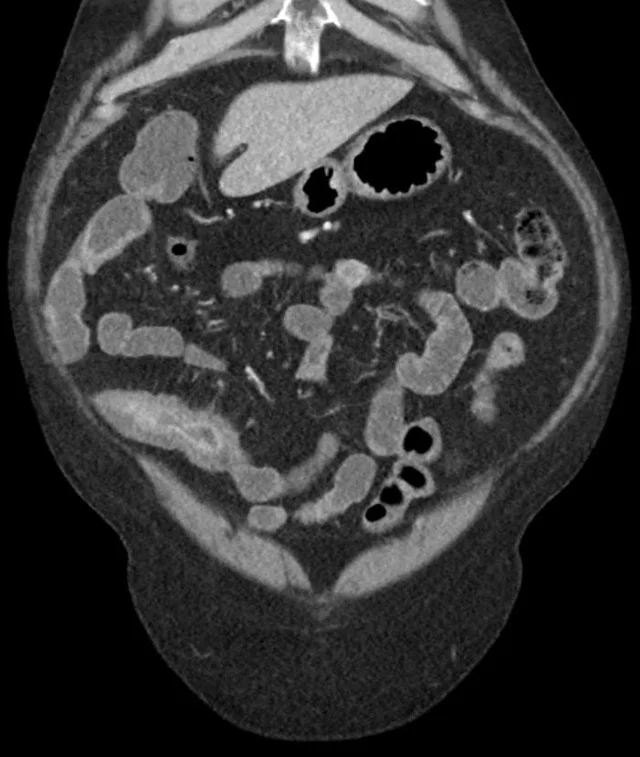

每当我想起那些在X光片上蜿蜒曲折的线条,我的心就忍不住揪成一团。克罗恩病,这个听起来既陌生又让人心生畏惧的名字,它的X线表现就像是命运在人体内肆意涂鸦的痕迹。

想象一下,那些线条如同顽皮的孩子,在肠道壁上留下不可磨灭的印记。它们或直或弯,或粗或细,每一道都像是诉说着一个不为人知的故事。有时候,它们聚集在一起,形成一个个小坑洼,仿佛是肠道在无声地哭泣,诉说着它们的疼痛和无奈。

更让人心痛的是,这些线条并不孤单,它们常常伴随着肠道的狭窄和瘘管的形成。这些变化,就像是一场场无情的战争,在人体内部悄然上演。每一次检查,都像是在揭开一层层伤疤,让人既期待又害怕。